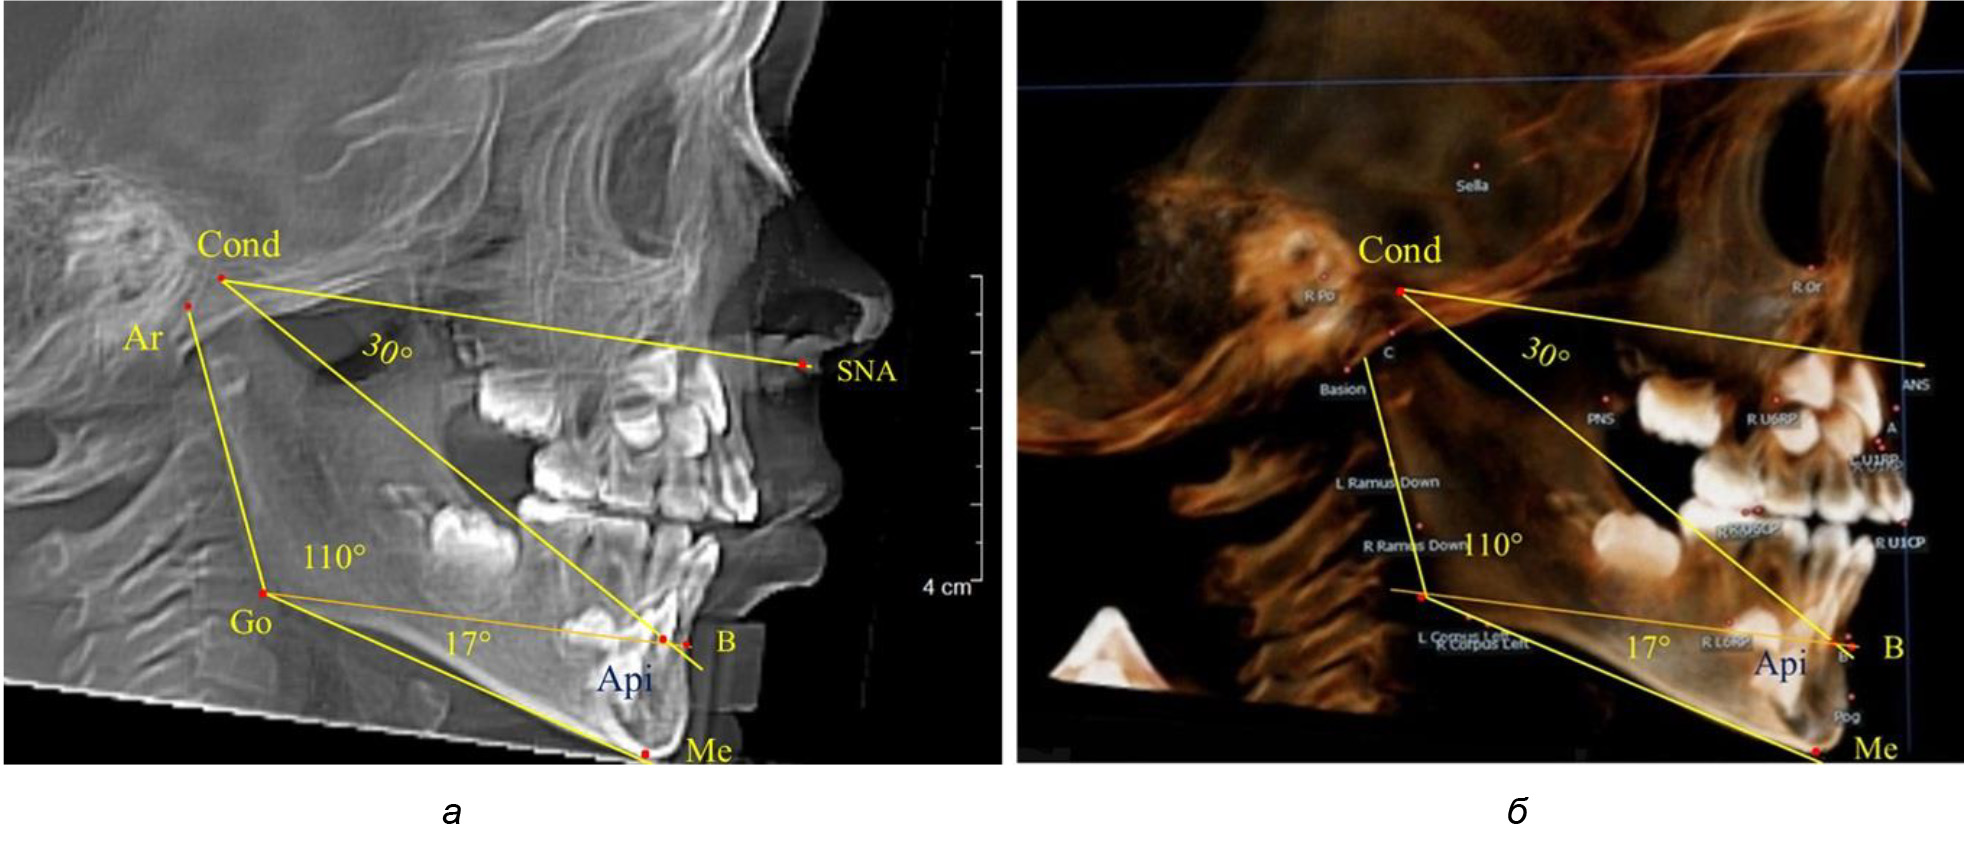

Рис. 1. Расположение реперных точек (а) и линий (б) для оценки угловых параметров гнатической части телерентгенограммы

Особенность анализа телерентгенограммы в периоде сменного прикуса заключалась в том, что наслоение зачатков постоянных зубов затрудняло определение апикальной точки нижнего резца. В подобных случаях использовали метод совмещенного анализа телерентгенограммы с фрагментом томограммы, на котором, также как и на телерентгенограмме, определяли положение резцовой и апикальной точек с построением условной вертикали, которая служила ориентиром для совмещения фрагментов (рис. 2).

При анализе ТРГ 5 детей в периоде прикуса молочных зубов отмечено, что величина основного угла гнатической части лица SNA-Cond-Api, как правило, в норме составляла около 30°, и его величина была относительно стабильной у всех обследованных детей. В то же время угол нижней челюсти и его составляющие отличались вариабельностью параметров при различных показателях нижнечелюстного угла (рис. 4).

Рис. 4. Особенности ТРГ (а) и 3D-модели (б) в периоде прикуса молочных зубов

Таким образом, в периоде молочного прикуса с оптимальными окклюзионными соотношениями, несмотря на линейные размеры в вертикальном и сагиттальном направлении, которые, безусловно, меньше параметров взрослых людей, величина основного угла гнатической части лица SNA-Cond-Api соответствовала параметрам людей с полностью сформированным физиологическим прикусом постоянных зубов. Анализируя данные рентгенограмм детей в периоде сменного прикуса, отмечено, что величина основного угла гнатической части лица SNA-Cond-Api, так же как в молочном и постоянном прикусе, в норме составляла от 28 до 32°. В то же время угол нижней челюсти и его составляющие отличались вариабельностью параметров при различных показателях нижнечелюстного угла. Достоверных различий угла гнатической части после смены нижних медиальных резцов и прорезывания первых постоянных моляров (4 ребенка) не было; происходил очередной этап подъема высоты прикуса и увеличение линейных размеров костей гнатической части, однако угловые параметры были относительно стабильны. После смены всех резцов и замены первых молочных моляров первыми премолярами (6 человек) увеличивались линейные размеры при сохранившихся угловых показателях гнатической части лица (рис. 5).